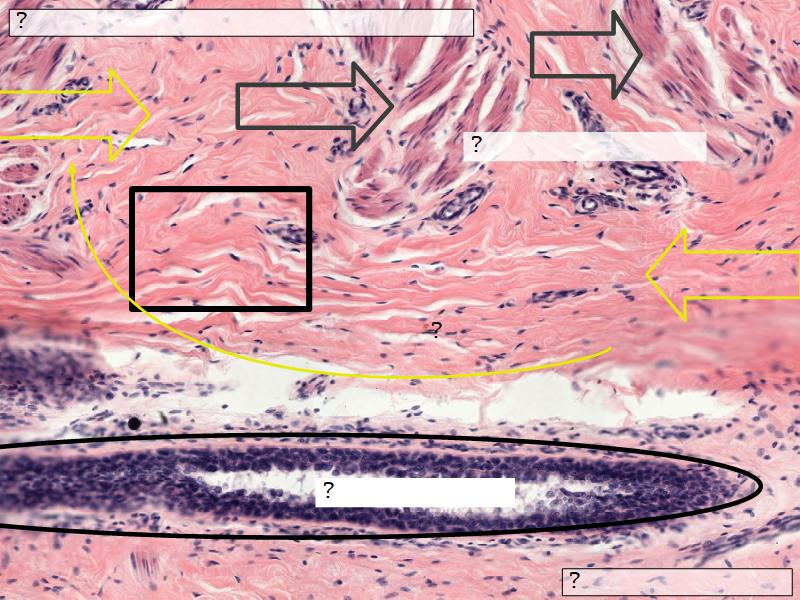

Structures

List the structures and cells found in the mammary gland.

Structures

- Lactiferous sinuses

- Stratified squamous near opening on skin

- Stratified cuboidal other parts

- Lactiferous ducts

- Stratified cuboidal

- Myoepithelial cells

- Underlie lactiferous ducts in most areas

- Basal lamina

- Separate epithelial components from stroma

Stroma

- Collagenous connective tissue

- Irregular dense connective tissue

- Smooth muscle

- Fibres and bundles

- Lactiferous sinusses

- Stratified cuboidal epithelium